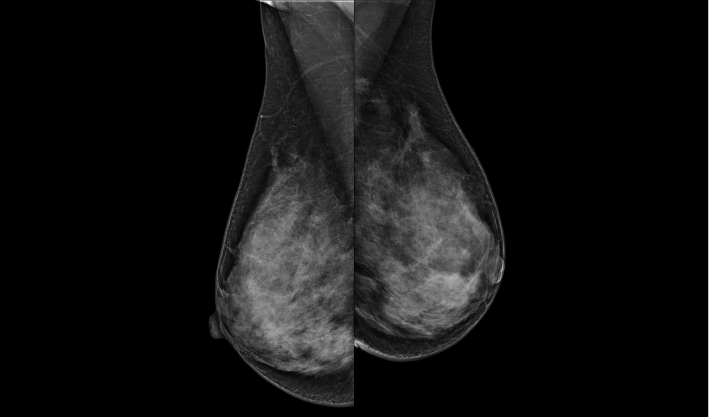

头尾位(CC位) 内外斜位(MLO位) 补充体位(根据需求)

一键式视图切换